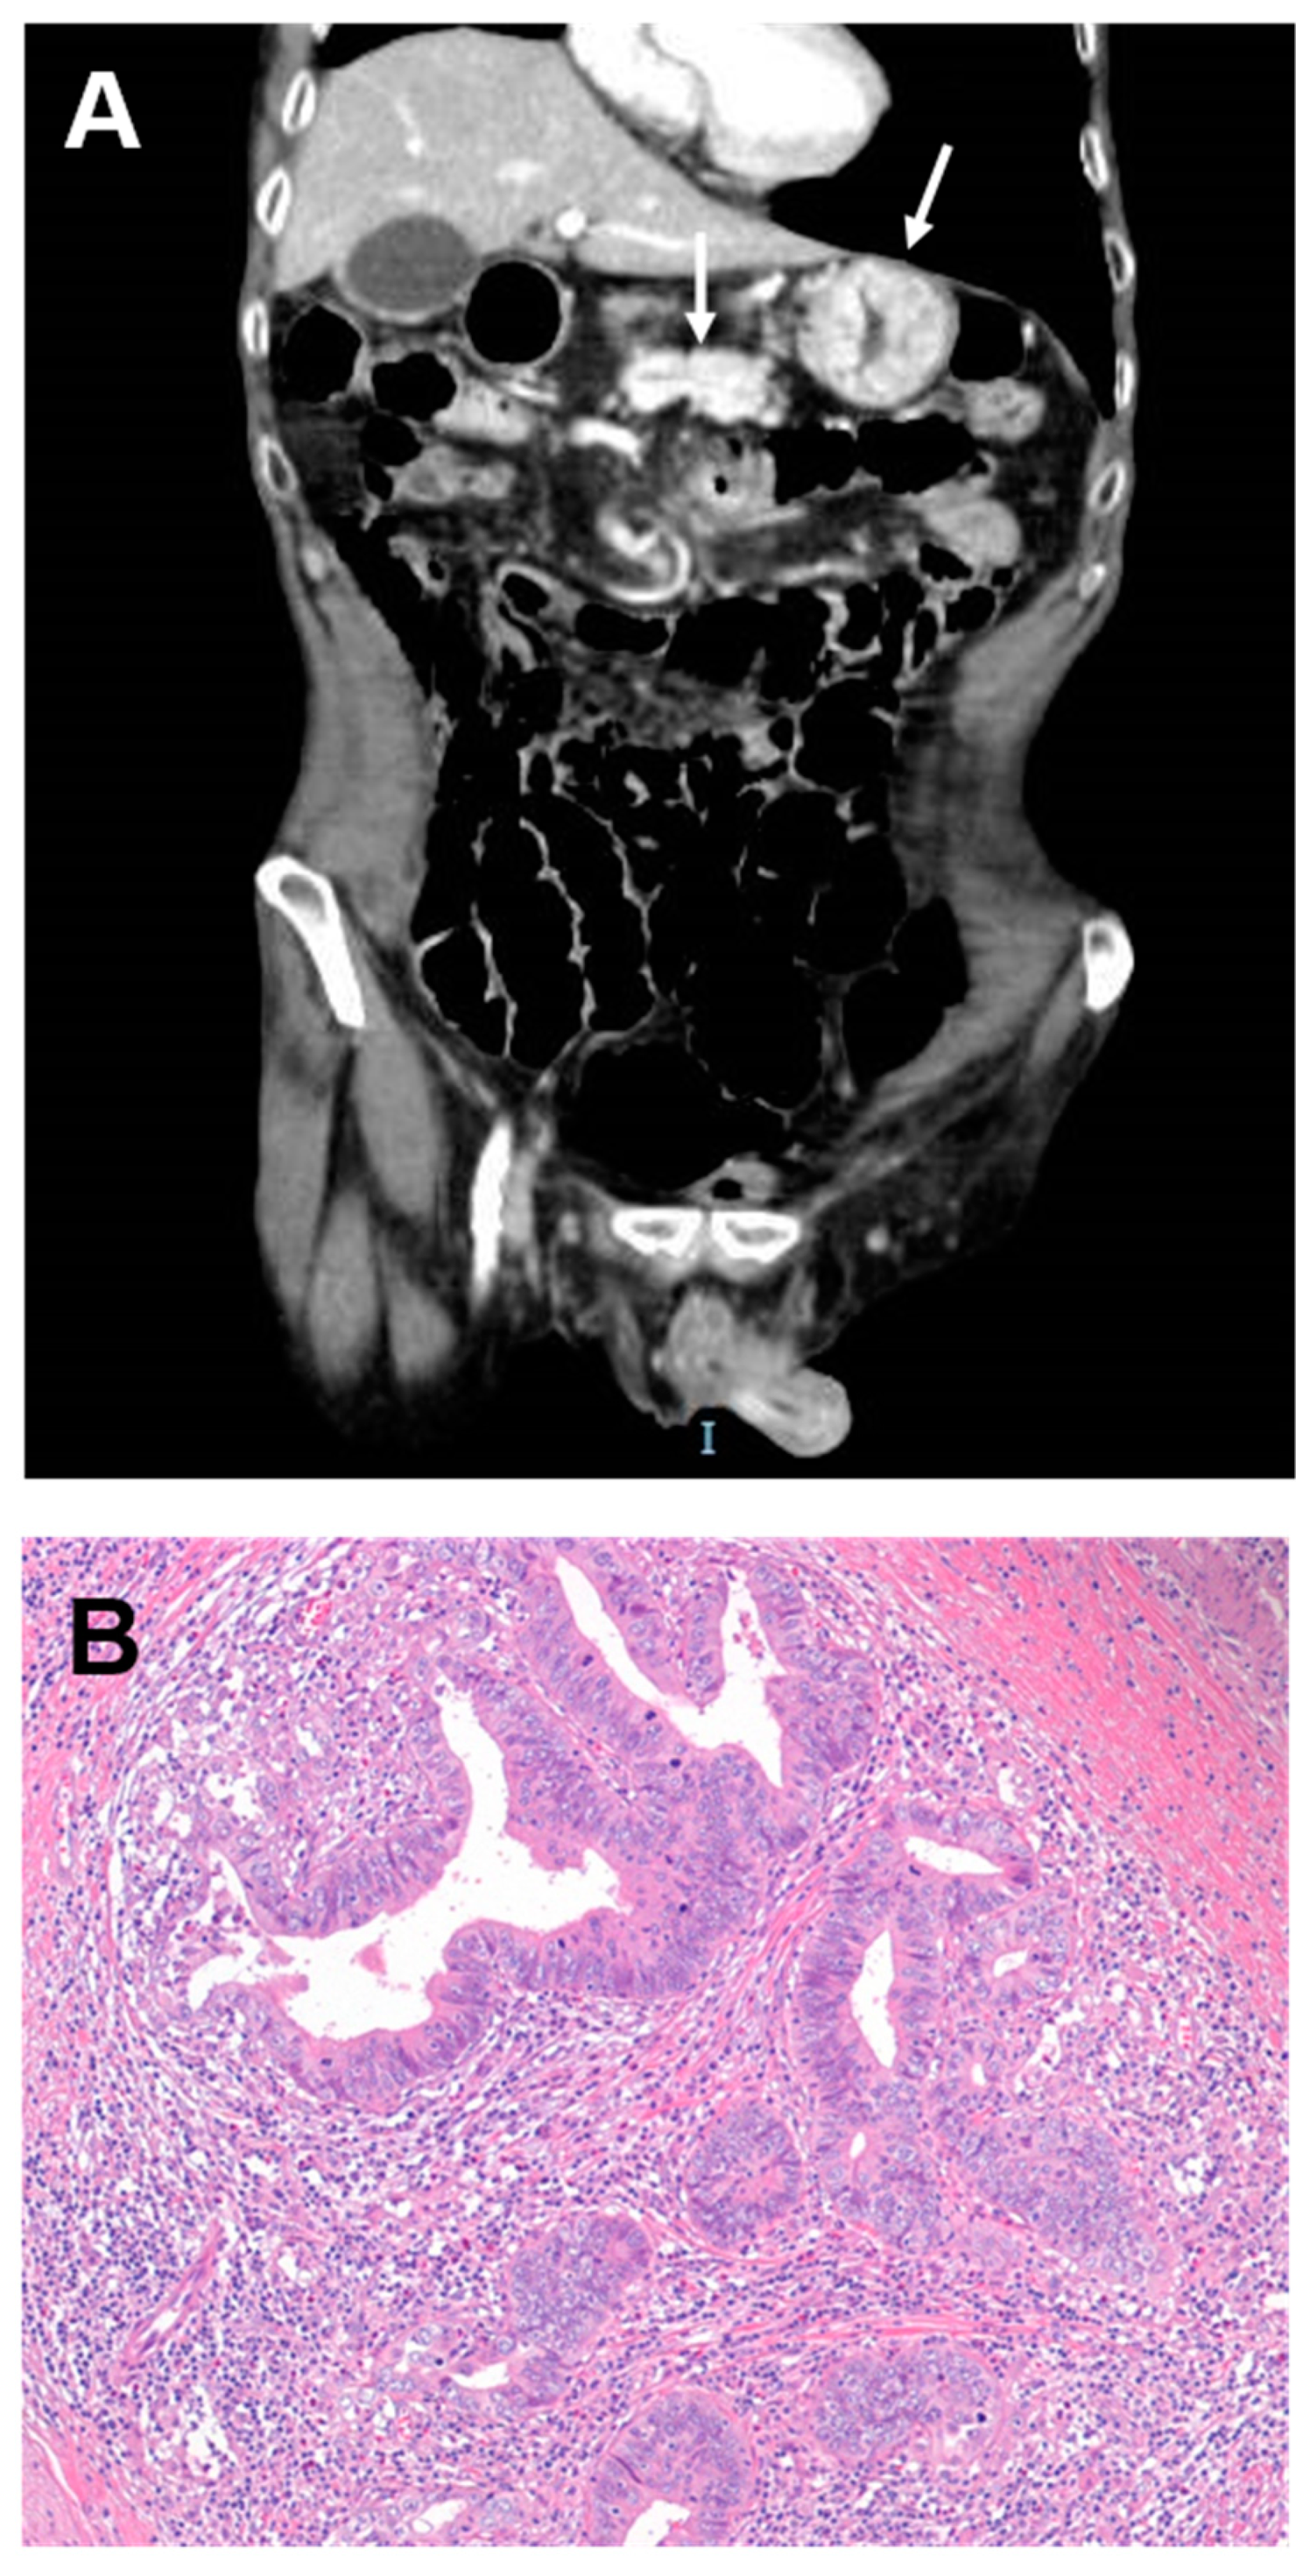

| Weber NK et al., 2015 [21] | 34 | 52.9, 32–74 | 22.4, 13.0–69.3 | 22.3, 0–50.6 | NA | 52 at 2 yrs | Imaging features suggestive for CrD-SBC included annular mass, nodularity at the extraluminal margins of mass, and perforation |